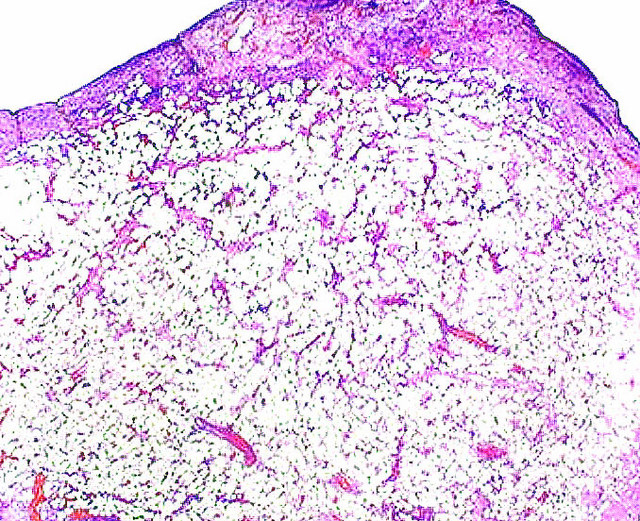

Points of Recognition

- 1Lobules of mature adipocytes

- 2Peripheral (compressed) nuclei

- 3Thin fibrous capsule

- 4Absence of atypia or lipoblasts

- 5Capillaries often present between adipocytes

Lipoma is the most common benign soft-tissue tumour in adults, composed of mature adipocytes arranged in lobules separated by delicate fibrovascular septa. It is characterised by clear cytoplasm and peripherally displaced nuclei with no atypia, mitoses, or lipoblasts.

- Lobules of mature adipocytes with clear (lipid-filled) cytoplasm

- Peripherally located, small, flattened nuclei โ no atypia or hyperchromasia

- Delicate fibrovascular septa separating lobules

- No lipoblasts (distinguish from well-differentiated liposarcoma)

- No increased mitotic activity

- May have thick fibrous capsule or blend imperceptibly into surrounding fat